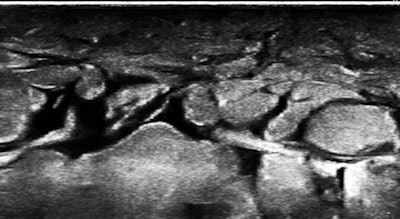

About the same time that we saw the first case, an adult male patient was referred for a vague reason that seemed to have something to do with morbid obesity and failure to lose weight, except through the use of diuretics. He had been hospitalized a few months earlier with pneumonia. The patient was very pleasant but quite enormous, and I really worried that I would not be able to see much with my equipment.

However, as soon as the probe touched the right upper quadrant (I tend to start everything with the liver), it was obvious that there was massive ascites with no increase in abdominal wall or other fat. The fluid was echo-free, and there were no peritoneal studs. The liver and kidneys appeared normal, hepatic veins were patent and normal in caliber, and a brief cardiac survey was normal as well. In a few minutes of scanning, there was a major finding that was a complete surprise and most of its most serious causes were eliminated from consideration. I just love the diagnostic power of ultrasound, especially in a completely exploratory role.

The skin of the lower abdomen is bubbly from lymphedema, and there was a large subcutaneous, paraumbilical sac that opened into the peritoneal cavity.

Remember the lab dogs with surgical ascites? If you had been diligent in your reading about lymphatics, you would have come across the fact that the most common cause of ascites globally is filariasis, afflicting more than 100 million people where mosquitoes are infested with Wuchereria bancrofti and Brugia malayi. The parasites gain entry into superficial lymphatics and propagate centrally, leaving occluded channels in their migratory wake.

So, of course, we had a look at the thoracic duct, which had an abnormal appearance (image below). The technique of visualizing the terminal portion of the thoracic duct, adjacent to the left jugular vein, was published by Seeger et al (Radiology, September 2009, Vol. 252:3, pp. 897-904).

Filariasis usually afflicts legs or genitals, ascending from infections acquired from walking barefoot through an infested area. Our patient happened to be an armorer and professional rifleman who had used a prone firing position when instructing in the tropics, hence the anterior lower abdominal entry of the parasites.